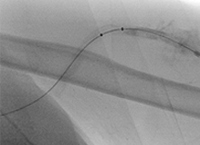

Acute DVT left lower extremity revascularization

47 year old male presented with leg swelling ~2 weeks.

Procedural steps

• Power Pulse delivery of 10mg tPA followed by

• 20 minute dwell time

• Total runtime was 300 seconds

Acute DVT Left Lower Extremity Revascularization pre-treatment angio.

Acute Iliofemoral thrombus pre-treatment

IVC Filter placed (left image)

Acute DVT Left Lower Extremity Revascularization post-treatment.

Post ZelanteDVT  pharmacomechanical thrombectomy

Case images courtesy of David Wilson M.D. – Harbin Clinic, Rome, Georgia – December 19, 2015